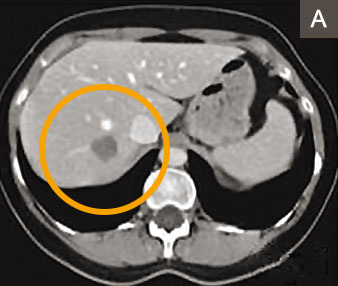

Alternativ oder ergänzend zur Leberteilentfernung können Lebertumoren auch mit einer Nadeltechnik 2 verödet werden. Dabei erzeugen Radiofrequenzen oder Mikrowellen hohe örtliche Hitze. Die Methode ist für nicht oberflächlich gelegene Lebertumoren bis zu einer Grösse von drei Zentimetern geeignet (Abbildungen A – C). Sie wurde vom Autor und seinem Team seit 15 Jahren angewandt und weiterentwickelt 3 und bietet folgende Vorteile: Es geht weniger normales Lebergewebe verloren als bei der Leberteilentfernung und der Eingriff kann ohne Bauchschnitt durchgeführt werden. Entsprechend ist die Nadeltechnik für die Patienten wenig belastend.

Computertomographie-Bild mit einzelner Metastase (grauer Fleck) im rechten Leberlappen